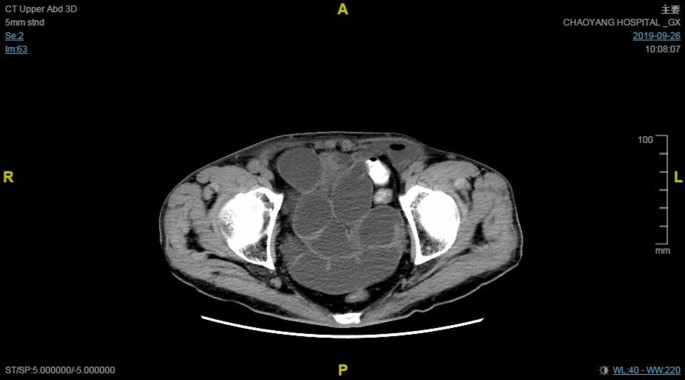

A 73-year-old man was admitted after having undergone bilateral TAPP with 3DMax mesh (C. R. Bard, Inc., Murray Hill, NJ, USA) at a secondary hospital 22 days previously. The mesh had been fixed by medical glue (Compont Medical Devices Co., Ltd., Beijing, China), and the peritoneal flap had been closed with interrupted suture. The patient had experienced abdominal distension since postoperative day 6. After conservative treatment, his symptoms did not substantially improve. CT scans showed multiple distended bowel loops, exudates in both groin areas, and air-fluid levels in the left preperitoneal space (Fig. 1).

Early diagnosis and proper treatment are the keys to a successful outcome in patients with post-TAPP SBO. The diagnosis of SBO is based on a clinical examination and routine radiological imaging. CT is necessary to distinguish the causes of obstruction, and its sensitivity and specificity may reach 90% [20].